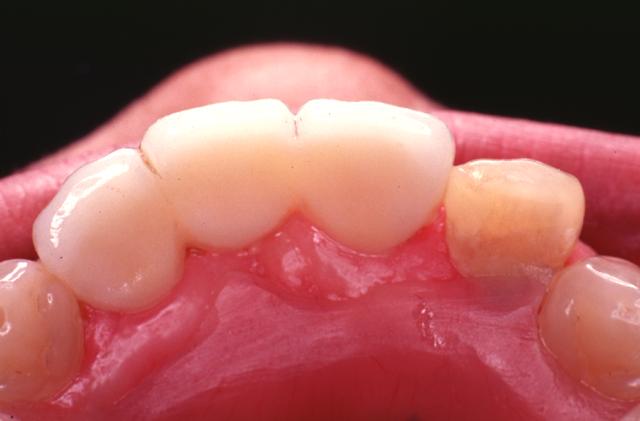

インプラント治療は、歯が抜けてしまった部分に人工歯根を埋入し人工歯をかぶせる治療法です。

インプラント本体は手術によって顎骨に埋め込みますが、顎の骨としっかりと結合・固定されるため、健康な自分の歯のようにしっかりと噛むことができるように機能性が回復します。

インプラント治療は、失った歯が1本から数本のケース、全歯が無く総入れ歯が合わないようなケースなどに対応しております。

また、4~6本のインプラント本体を埋め込み、インプラント専用の義歯を固定する治療も可能です。